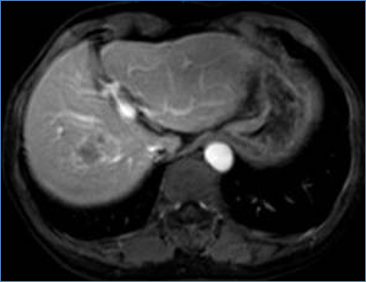

CT image of liver after the MWA treatment

Enhanced CT one month after ablation